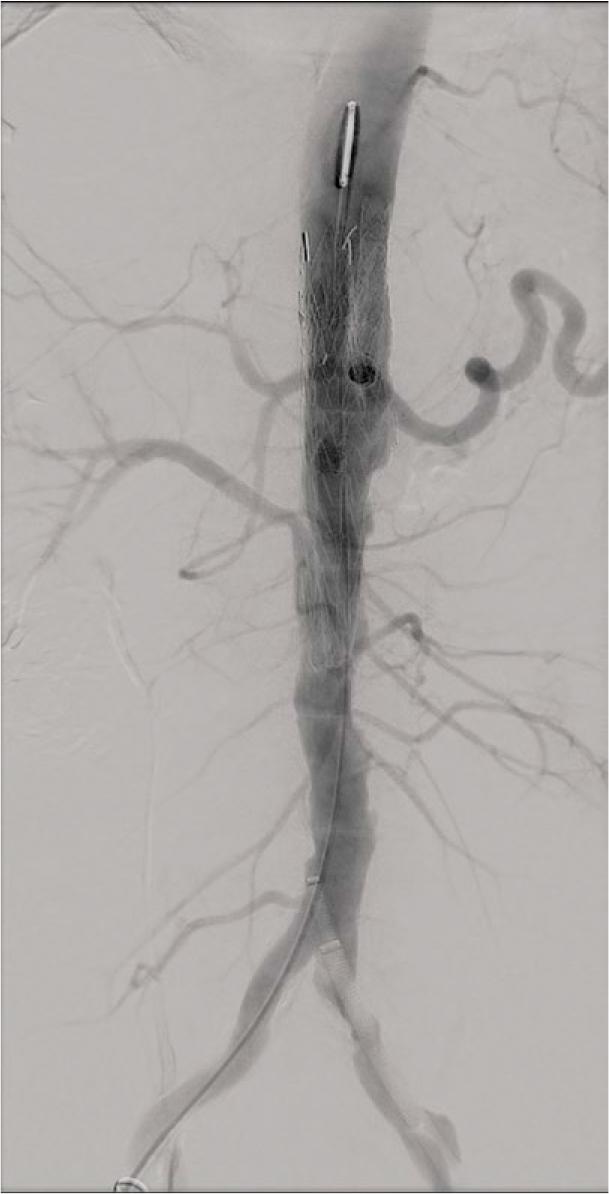

FIGURE 3.